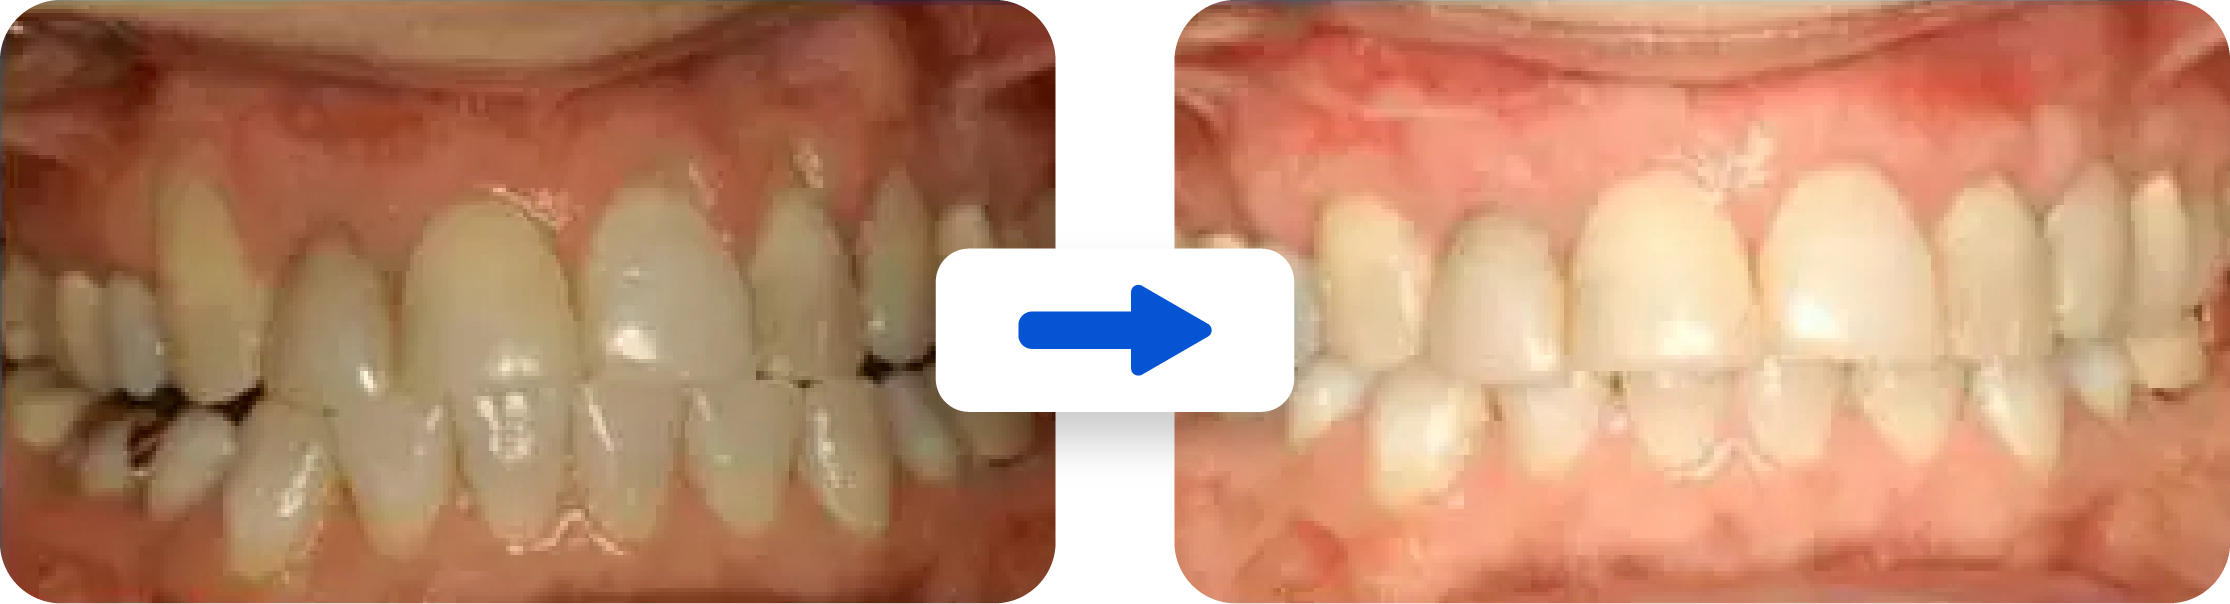

The Below Picture Shows Root Cavities Treated with Soft Tissue Grafting.

Soft Tissue Grafting Is Highly Predictable

Gum grafting is 95% successful. The first goal of soft tissue grafting is to produce a stable healthy band of attached gum tissue around the tooth. This increased thickness of gum tissue prevents further loss of gum tissue and bone and helps you to keep your tooth/ teeth. In fact, gum grafting has been shown to regrow up to 50% of the bone around a tooth. The second goal is to cover the exposed portion of the root as much as possible. This can be aesthetically pleasing. If teeth are sensitive, then soft tissue grafting may cover the root to prevent root sensitivity.